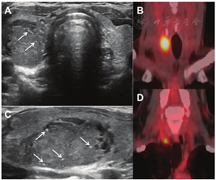

4.超声检查。甲状腺超声显示不均匀、弥漫、低回声和混合回声,彩色多普勒图像上血流信号无明显增加[86]。当病情缓解时,这些异常表现通常会恢复到接近正常(图7)。

5.放射性核素显像。在甲状腺毒症期,甲状腺显像的特征是甲状腺组织显像剂摄取非常低或不显影,这也是其他破坏性甲状腺炎的特点。(例如:Ⅱ型胺碘酮诱发性甲状腺功能障碍)。根据疾病的不同阶段,可表现为整个腺体或部分腺体放射性分布缺损。即使亚急性甲状腺炎主要累及甲状腺的1叶,甲状腺显像也可能表现为整个腺体完全没有显像剂摄取(图7),这是因为在甲状腺毒症期TSH水平受到抑制。